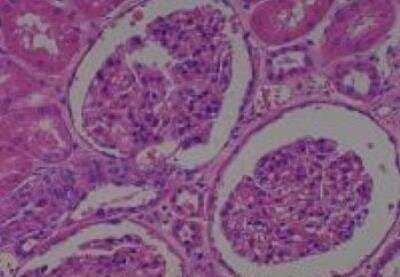

Scientific Data Images for Human Multi Tissue MicroArray (Normal Adjacent)